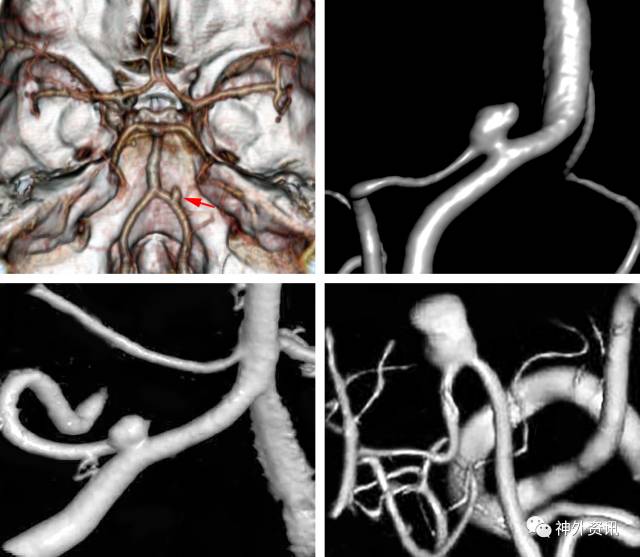

CT血管成像对于显示周围血管的组成,与后颅窝的骨质,包括枕骨大孔和斜坡的关系等,都提供了有效的信息。中线附近的动脉瘤常与后循环的扩张有关,这对显微手术提出了很大的挑战,在这种情况下可以选择血管内治疗。

图1:上图显示的是中线附近的PICA动脉瘤。左下图显示的是更加经典的近心端PICA动脉瘤,右下图显示的是远端脉络膜前动脉瘤也出现在同一个病例中。值得注意的是PICA在动脉瘤颈处起源。